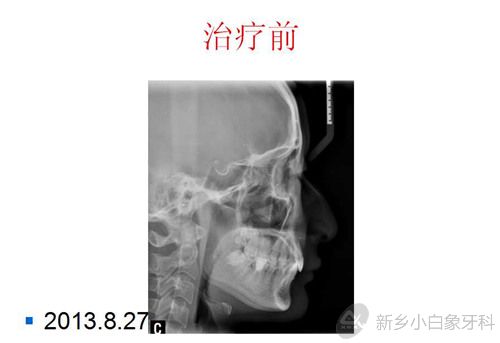

患者张某某,女,21岁,近期感觉牙齿不齐,影响美观,于2013年8月27日来我院就诊。

X线检查:18、28牙胚发育良好,38、48近中阻生,36、46牙冠及根管内见白色充填物。

问题清单:安氏二类错颌,内倾型深覆颌,12、22牙冠发育过小,个别牙不齐,38、48近中阻生。